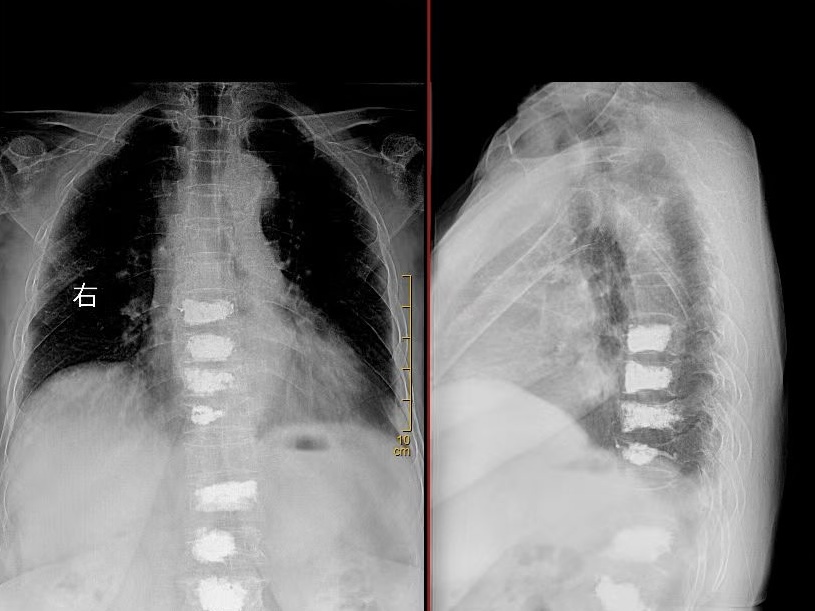

术后DR

骨水泥椎体成形术是一种微创手术,具有创伤小、恢复快、住院时间短、手术时间短等优点。手术在局部麻醉下进行,通过穿刺针将骨水泥注入骨折椎体,增强椎体强度和稳定性,从而达到缓解疼痛、恢复椎体高度的目的。手术过程非常顺利,仅用时30分钟。术后,赵奶奶的疼痛症状明显缓解,即刻下床活动,术后第三天便康复出院。